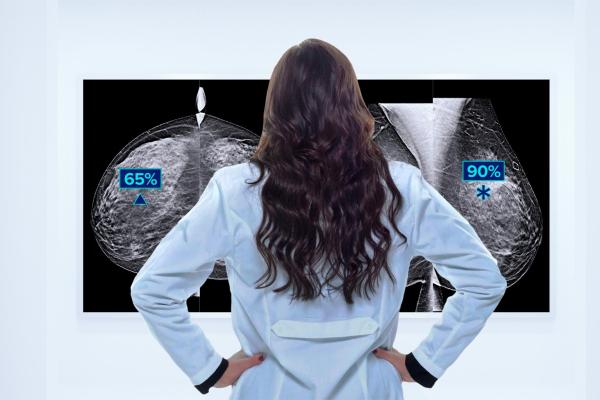

Women’s health imaging solutions from Hologic which aid in cancer detection and radiologist workflow were part of the Radiological Society of North America Scientific Sessions and Annual Meeting, RSNA 2023, held this week in Chicago. Image courtesy: Hologic

New to Hologic’s portfolio of Breast and Skeletal Health Solutions: Genius AI Detection 2.0 solution, a next-generation deep-learning technology designed to improve breast cancer detection while reducing the number of false-positive markings per case. With more than a 70% reduction in false-positive markings per case when compared to Hologic’s ImageChecker CAD solution, Genius AI Detection 2.0 technology gives radiologists confidence that marked lesions are truly suspicious and warrant further review.1 Additionally, the new SecurView 12.0 solution enables more multimodality capabilities, including reading breast ultrasound cases directly in the SecurView viewer. When paired with Genius AI Detection 2.0, the new automated lesion correlation feature is enabled to allow for faster review of specific lesions, according to a company overview.